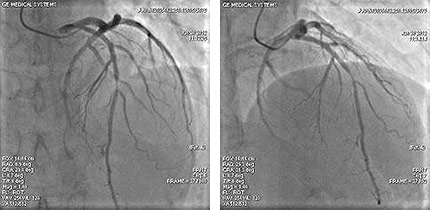

![]() |

| 冠動脈撮影 |